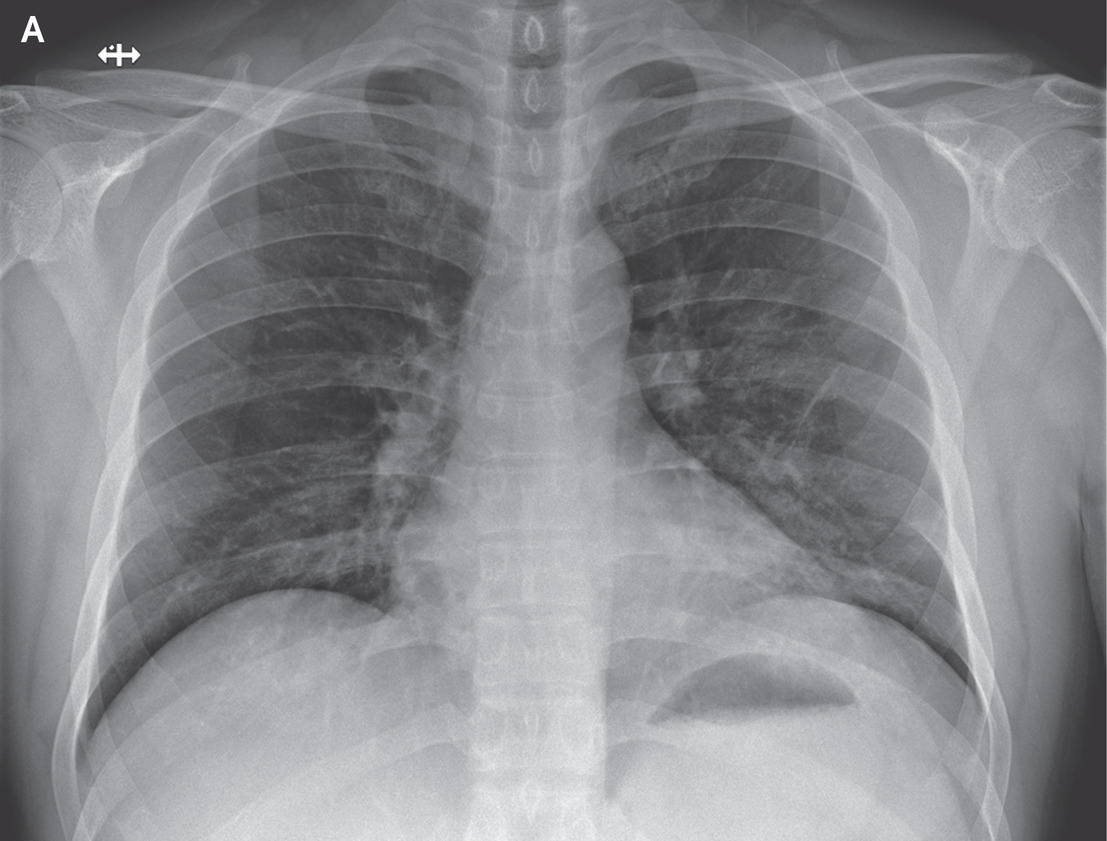

Two datasets DS1 and DS2 were constructed using extracted data from the above two data repositories for training and testing proposed model and other pre-trained models. DS1 includes about 150 CXR of Covid-19 and 150 CXR of normal subjects which was designed for binary classification problem. DS2 was designed for three class classification where we differentiate Covid-19 infected subjects from normal and other pneumonia type infections. This dataset consists of 150 Covid-19, 150 other pneumonia and another 150 instances for normal CXR images. Within the samples of other pneumonia CXR, there are cases of bacterial infections, fungal infections and other viral infections of subjects. Figure 1 presents representative CXR images for Covid-19, bacterial, fungal, other viral and normal patients respectively.

\zihao-5Fig. 1: \zihao-5Representative CXR images from datasets corresponding to different infections

In these sample CXR images, there are certain areas with hazy opacification or increased attenuating as these areas are filled with some substances other than air. This is an indication of displacement of air by fluid and a collapse of periphery of lungs due to various infections. Though these areas are visible as more grey and cloudy compared to darker areas with lower attenuation, differentiating the cause of infection is not possible for human eye alone. Further, the specific radiographic patterns can be variable depending on different viral strains making it hard even for expert to diagnose using CXR alone. This further implies the demand for efficient and accurate automated CXR based techniques for disease diagnosis.